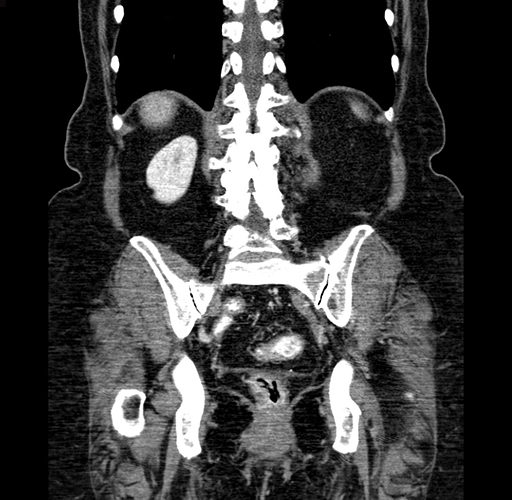

Pre-Chemo: Coronal Venous

Coronal Venous